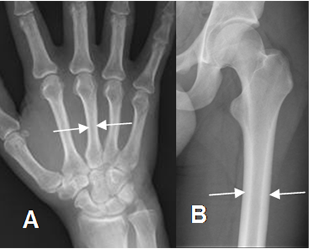

Fig 40. Osteoporosis.

A: Rx AP de muñeca y B: Rx AP de hombro. Signos de osteoporosis, con adelgazamiento en las corticales de los huesos.